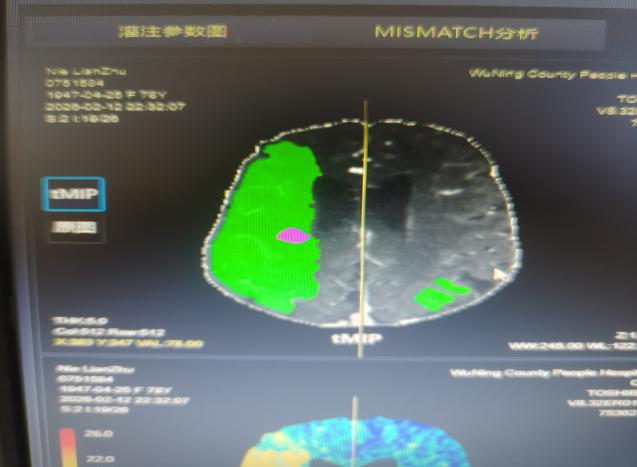

“时间就是大脑,每延迟一分钟,就有190万个神经细胞不可逆坏死!”面对紧急病情,医护团队争分夺秒。快速完成头颅CT等检查后,明确患者符合静脉溶栓指征且无绝对禁忌证,与家属协商签署溶栓同意书后,于22:04立即对患者进行阿替普酶溶栓治疗,DNT时间仅34分钟。然而,溶栓后复查影像学显示,患者大脑中动脉主干仍大血管闭塞,单纯溶栓未彻底开通血管,病情高危。关键时刻,救治团队当机立断,决定采用当前急性大血管闭塞性脑卒中的前沿救治方案——“溶栓桥接取栓”,为患者打通生命通道。

手术室内,神经内科张奕主任凭借丰富经验和精湛技术,在数字减影血管造影机引导下,经毫米级微创通道,将取栓器械精准送达闭塞血管核心部位。经不到1小时操作,成功完整取出堵塞血管的栓子,闭塞血管再通,脑部血供恢复。术后复查头颅 CT显示低灌注区脑组织全部存活。